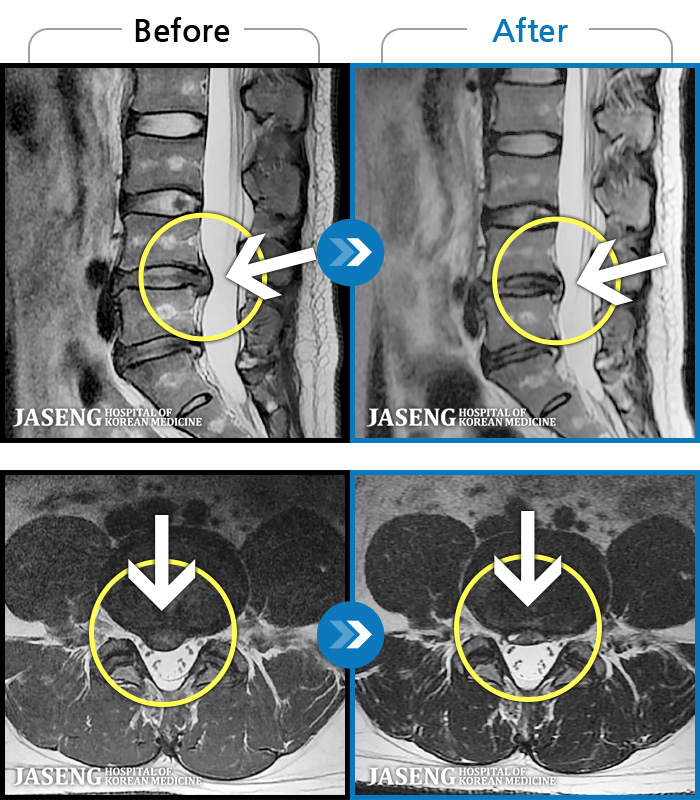

MRI ġ

1,245 MRI ũ ʸ Ȯϼ.